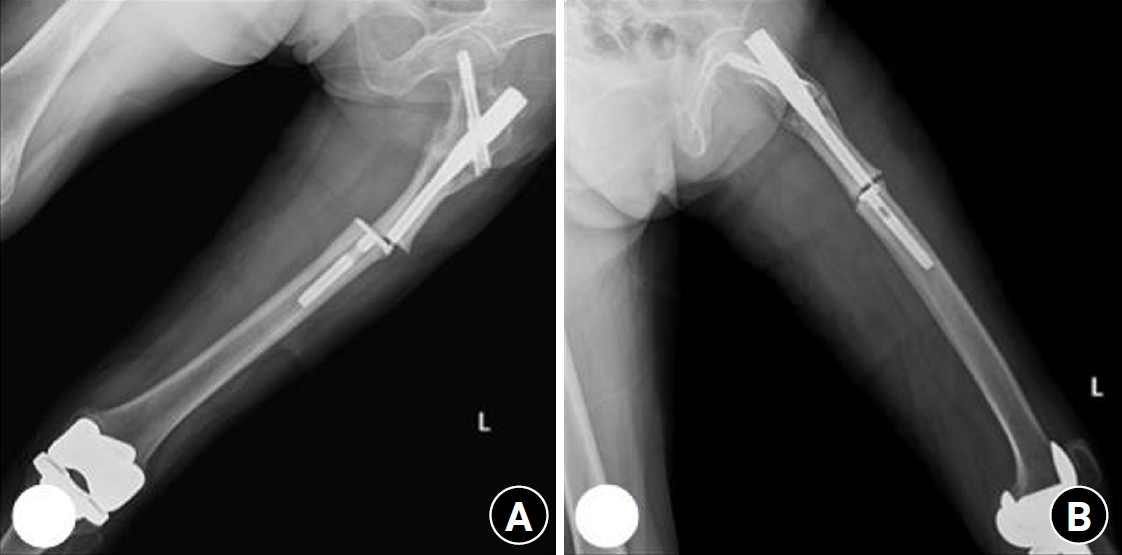

Previous studies have extensively examined the association between femoral insufficiency fractures and prolonged bisphosphonate therapy. However, alternative etiologies remain insufficiently characterized. This study aimed to analyze non-pharmacologic factors associated with femoral insufficiency fractures, with particular emphasis on paradoxical cortical hypertrophy and altered biomechanical load distribution. We reviewed three cases of femoral insufficiency fracture that were surgically treated at our institution between January 2018 and January 2022. None of the patients had a history of bisphosphonate use. Clinical histories—including underlying comorbidities, prior surgical procedures, and radiographic findings—were evaluated. Serial radiographs obtained before and after fracture occurrence were analyzed to characterize fracture morphology and associated cortical changes. Case 1 involved a patient with post-traumatic hip synostosis; case 2 involved a patient with osteogenesis imperfecta; and case 3 involved a patient who had previously undergone intramedullary nailing for an intertrochanteric fracture. Lateral femoral bowing and cortical hypertrophy preceded fracture development in two cases, whereas focal cortical hypertrophy at the distal locking screw site was observed in the third case. No history of bisphosphonate therapy was identified in any patient. Fractures developed at sites characterized by increased cortical remodeling and abnormal load concentration. Femoral insufficiency fractures can occur in the absence of bisphosphonate therapy. Paradoxical cortical hypertrophy and altered biomechanical force distribution appear to be important contributing factors. Level of evidence: IV.